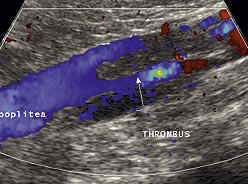

Beispiel eines Ultraschallbildes bei tiefer Beinvenenthrombose:

Gerinnsel = Thrombus in der Kniekehlenenvene